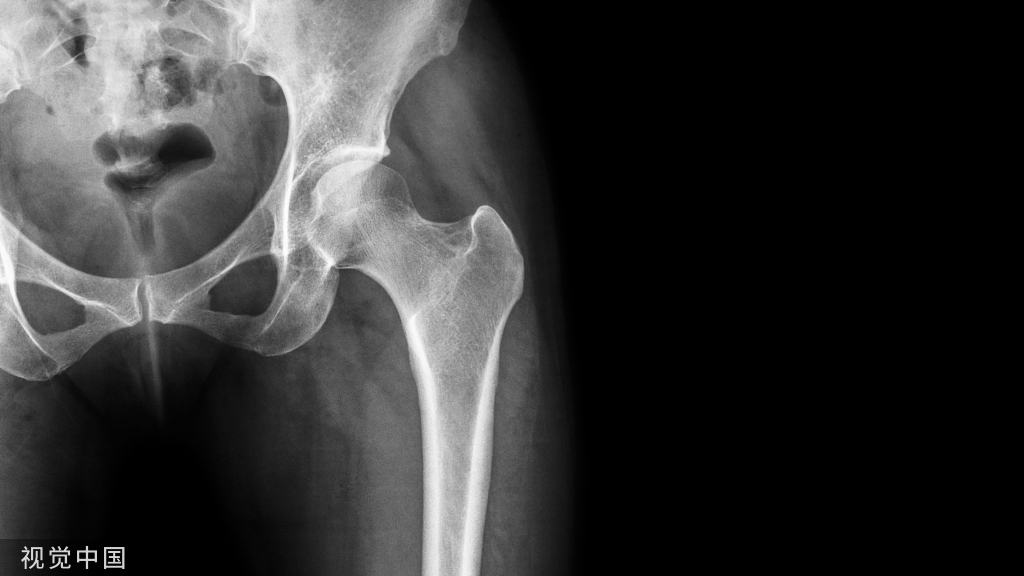

最后,孙永强教授和夏亚一教授就人工关节置换手术的未来发展方向进行了展望。大家认为,随着医学技术的不断进步,人工关节置换手术将会更加成熟和规范。同时,随着患者对医疗服务需求的不断提高,手术的个性化与精准化将成为重要的发展方向